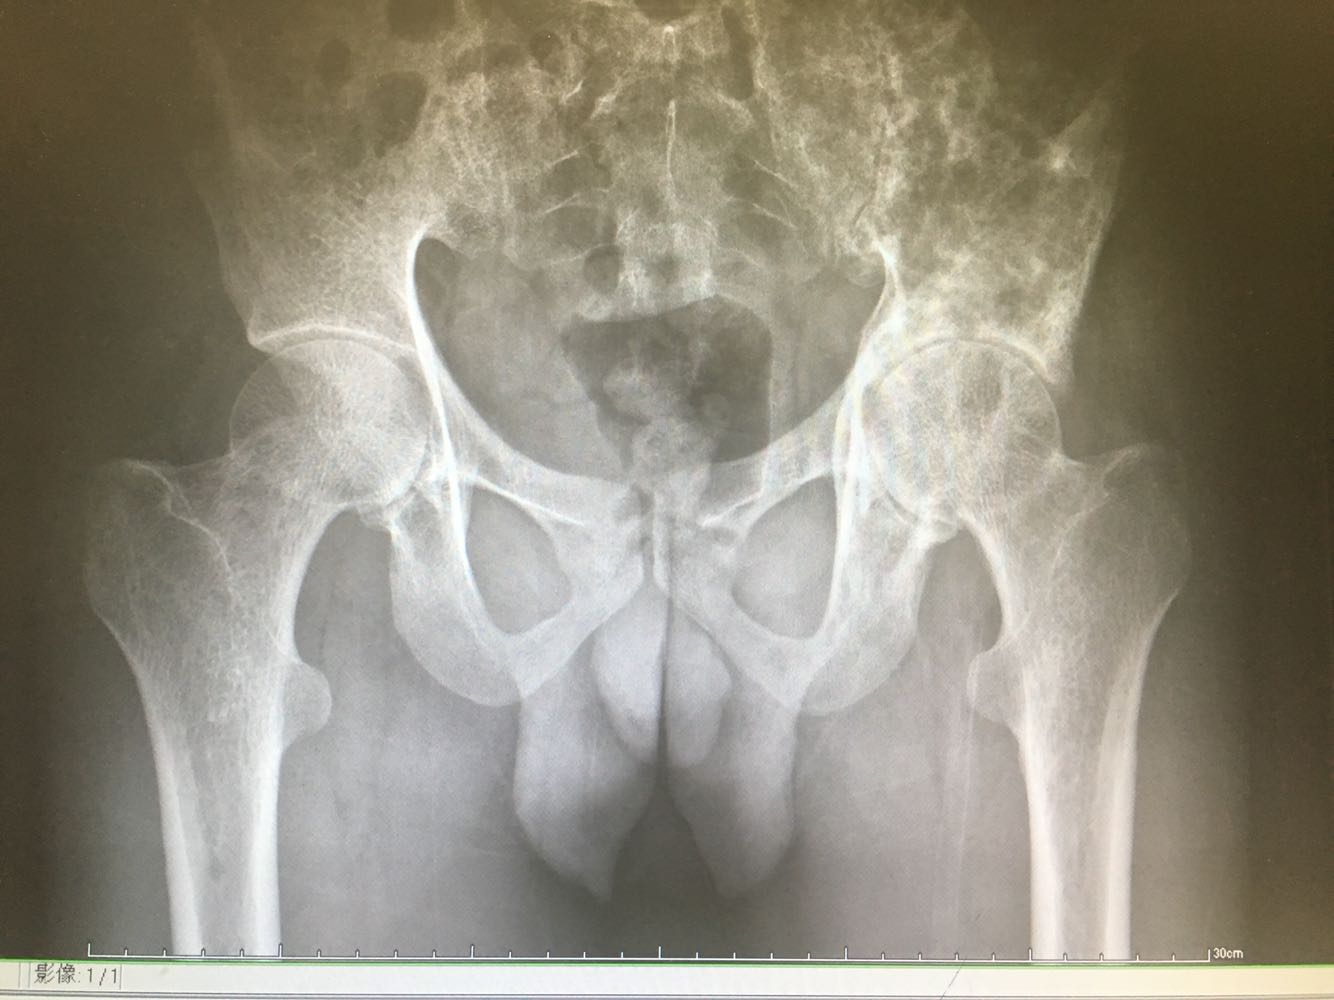

患者,男性,28岁 主诉:左髂疼痛3月 现病史:患者于3月前无明显诱因出现左髂疼痛,行走时加重,休息后缓解,未予重视,1月前发现左腰骶部一质硬肿块,遂至我院门诊就诊,查骨盆X片示:左髂骨骨质改变,现为进一步诊治收治入院,发病以来,神清,精神可,胃纳夜眠可,二便无殊,体重无明显变化。

查体:左髋部轻压痛,髋关节轻度活动受限,左踝、左膝关节活动正常。 辅检:见现病史

诊断:髂骨肿瘤(左侧) 治疗:进一步完善相关检查后行活检明确诊断,考虑恶性肿瘤。